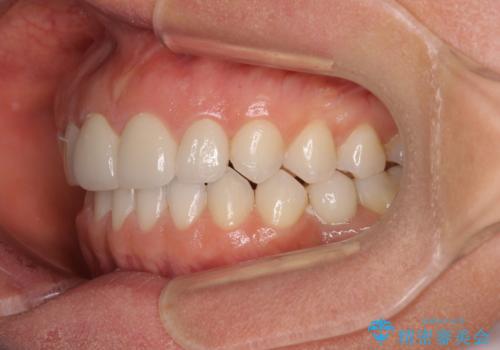

- 大きすぎる上顎前歯と、隙間の空いた下顎歯列を気にして来院された患者様です。

上顎前歯にはセラミッククラウンが装着されており、顔や他の歯と比較して幅の大きい状態でした。

下顎前歯は空隙歯列弓であったので、アンカースクリューとワイヤー装置を用いてスペースを閉じていくこととし、上顎前歯は矯正治療用の仮歯に置き換えた上で、仮歯の大きさを削って小さくしながら、上下前歯部の部分矯正を行うこととしました。